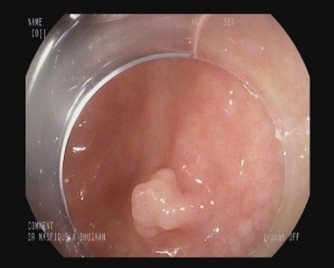

Colonoscopy image datasets are inherently heterogeneous, containing frames acquired under a variety of clinical conditions. As illustrated in Table 4, the data frequently exhibit artifacts that complicate polyp detection and segmentation. Examples include stool residues adhering to the intestinal wall, blood obscuring mucosal surfaces, or inflammation that alters tissue appearance. Additional challenges arise from image acquisition itself, such as low brightness, chromatic aberration, motion blur, or the presence of surgical tools in the field of view.

Table 4: Challenging Polyp image examples of BPD dataset.

Sl. no Image description Image Mask

1 Image containing polyp without any noise or challenging aspects [Uncaptioned image] [Uncaptioned image]

2 Image contains polyp with some stool dotting the intestinal wall [Uncaptioned image] [Uncaptioned image]

3 Image contains polyp with blood being present on the intestine wall [Uncaptioned image] [Uncaptioned image]

4 Image contains polyp in an inflamed intestine [Uncaptioned image] [Uncaptioned image]

5 Blurred or unfocused image containing polyp [Uncaptioned image] [Uncaptioned image]

6 Chromatic aberration distortion present in polyp image [Uncaptioned image] [Uncaptioned image]

7 Low brightness image containing polyp [Uncaptioned image] [Uncaptioned image]

8 Image with improper bowel preparation [Uncaptioned image] [Uncaptioned image]

9 Surgical tool present alongside polyp [Uncaptioned image] [Uncaptioned image]

10 Motion blur present in image [Uncaptioned image] [Uncaptioned image]